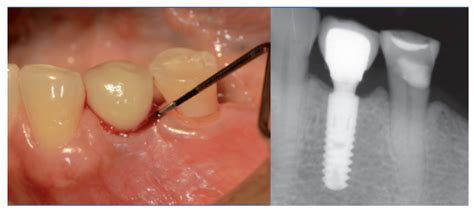

Periimplantitis

Si la mucositis no se trata a tiempo, puede progresar a periimplantitis. La periimplantitis es una infección seria que afecta no solo a la encía, sino también al hueso que sostiene el implante. En términos sencillos, es como una “periodontitis del implante”: además de inflamación y pus, aquí comienza la pérdida de hueso alrededor del implante.

La periimplantitis suele presentarse cuando la mucositis fue ignorada o persistió. ¿Qué la causa? Los mismos factores de la mucositis (placa bacteriana, mala higiene) potenciados en el tiempo. Además, ciertos pacientes tienen mayor predisposición, por ejemplo: personas con historial de enfermedad periodontal severa, fumadores intensos (el tabaco dificulta la circulación en encías y la respuesta inmune) o diabéticos mal controlados.

Un punto crítico es que la periimplantitis no siempre da grandes síntomas al inicio, por eso las revisiones periódicas son clave.

Síntomas de Periimplantitis

En etapas iniciales, los síntomas se parecen a los de la mucositis (encía inflamada, enrojecida, sangrado fácil y a menudo supuración de pus).

- Dolor en la zona.

- Movilidad del implante dental (debido a la perdida de hueso).

La periimplantitis no es reversible espontáneamente como la mucositis, pero se puede tratar para intentar frenar la infección y regenerar los tejidos en lo posible. El tratamiento siempre deberá hacerlo un profesional; en casa no podemos eliminar el problema solo con cepillado en esta fase.

En clínica, normalmente realizamos una limpieza profunda alrededor del implante (a veces con anestesia local), utilizando instrumentos especiales para eliminar el sarro y las bacterias de la superficie del implante. Muchas veces aplicamos antisépticos o antibióticos locales, e incluso antibióticos sistémicos (pastillas) si la infección lo amerita.